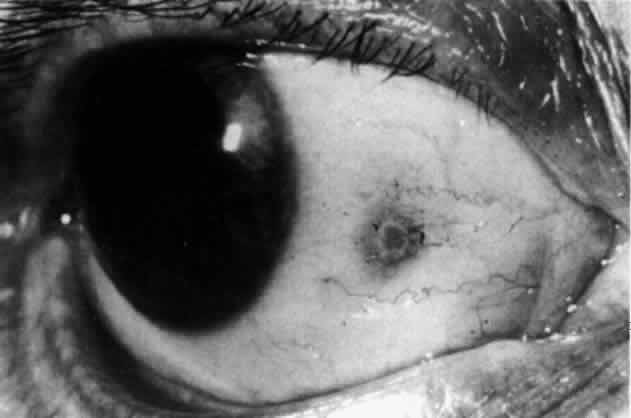

In contrast to simple episcleritis, the infiltration and edema of nodular episcleritis are localized to one part of the globe, forming a nodule and some surrounding congestion (Color Plate 1B). The nodule can be moved over the underlying sclera, which is not edematous. The scleral plexus of vessels can be distinguished deep to the nodule, lying flat on the sclera and slightly congested but otherwise normal in color and configuration (Figs. 15 and 16). Episcleral nodules may be single or multiple but do not undergo necrosis (see Fig. 16). After multiple attacks of nodular episcleritis in the same location, the superficial lamellae of the sclera show some alteration and become slightly more transparent in this one area. TREATMENT Even without therapy, simple episcleritis improves considerably within the first week and resolves within 3 weeks (Fig. 17). Provided the eye is not too uncomfortable, most patients can be persuaded to leave the eye untreated, because the condition will resolve spontaneously. However, if it is believed that some treatment is desirable, topical corticosteroids or locally applied nonsteroidal anti-inflammatory drugs (NSAIDs) may make the eye more comfortable and speed resolution slightly (see Fig. 17).9 Use of corticosteroid drops must be continued for several days after the inflammation has subsided to prevent the exacerbation of the condition that occurs if they are stopped suddenly. Prednisolone, betamethasone, or dexamethasone drops may be administered hourly until redness disappears, and then three times daily for 4 to 5 days. Under no circumstances should topical steroids be administered continually for more than a few weeks at a time because of the very real danger of inducing steroid glaucoma and cataract. If the condition fails to respond immediately, other treatment regimens should be sought. Ocular NSAIDs can be administered four times daily until redness disappears. Glaucoma and cataract have not been observed after prolonged use, but many patients become intolerant to the use of the ointment or complain of stinging and irritation. Whereas simple episcleritis resolves rapidly without therapy, the resolution of nodular episcleritis is much slower. Local therapy is consequently of much more value; the same regimen of treatment is followed. In the few patients in whom episcleritis becomes indolent, or in whom recurrences are so numerous that the patient becomes incapacitated, it is reasonable to consider systemic therapy with NSAIDs such as flurbiprofen (Froben), 100 mg three times daily, which usually gives immediate and prolonged relief of symptoms and signs. It is important to note that not all of the NSAIDs work in this condition. Treatment may be terminated abruptly when the condition comes under control. The complications of episcleritis are minor and are not responsible for any decrease in visual acuity. COURSE AND PROGNOSIS Whether treated or not, simple episcleritis will resolve in 10 to 21 days. It will usually reappear at irregular intervals and then eventually disappear. An accurate 12-month record kept by a patient who went without treatment is shown in Figure 18. He was free from any further attacks for 3 years. He then had four attacks in the next 3 months and has had none since. No etiologic or precipitating factor has been found. In nodular episcleritis, the nodule initially increases rapidly in size, sometimes reaching the size of a split pea. Thereafter it gradually regresses over a variable period and eventually disappears, although this may take up to 2 months without treatment. Recurrences occur also in nodular episcleritis, but the two varieties are not mutually exclusive (a simple episcleritis may recur as a nodular episcleritis and vice versa). However, episcleritis never develops into scleritis in the same attack, although it invariably accompanies scleritis. Of 180 patients initially diagnosed as having episcleritis, only 4 developed scleral involvement.10 Episcleritis is an entirely benign condition, although it may be a great nuisance to the patient. It may recur over a period of many years, but it rarely leaves any residual ocular changes except for some areas of scleral transparency or localized stromal keratitis in those patients who have had severe attacks of nodular disease occurring always at the same site. Of 180 patients analyzed,10 only 2% had a decrease in visual acuity of two lines or more within a year of the onset, and in every case this was from increasing involutional cataract. |